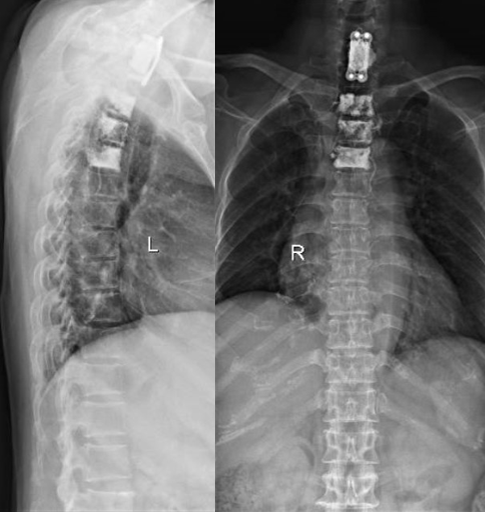

此为阿姨术后的X光,明亮处为骨水泥

张阿姨也一样,是肺癌晚期的患者,她和戴阿姨有着同样难忍的疼痛,不过张阿姨没有那么幸运,她转移癌的位置位于高位脊柱——颈椎,而且阿姨已经有了明显的双手肌肉力量减退、麻木、疼痛等表现,且颈椎较为特殊,如果单纯注入水泥的话,肿瘤在远期可能会进一步“啃食”我们的骨头,进一步加重骨质破坏,导致脊柱不稳,而颈椎后面走形的是我们比较高位的颈髓,如果出现压迫损伤,不仅会导致肢体的疼痛、麻木、无力,甚至导致四肢瘫痪,严重者呼吸肌无力,无法呼吸,如无及时抢救,甚至死亡。所以我们在手术注入骨水泥的同时,也会通过固定的钉棒系统,进行颈椎的固定,保持颈椎稳定性。

那么,我们来看看,戴阿姨和张阿姨的手术方式有什么不同吧!